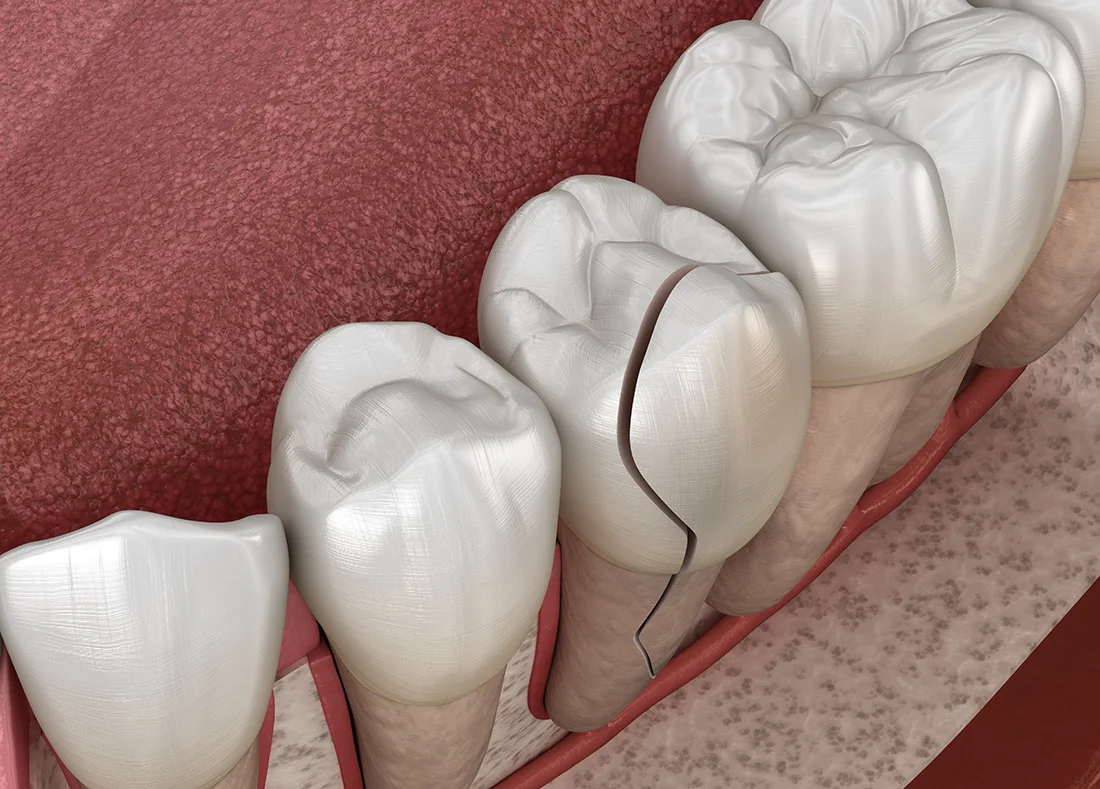

A toothache that lasts more than 1–2 days, especially if it’s throbbing, may be a sign of infection or an abscess. Try rinsing with warm salt water, applying a cold compress, and using OTC pain relief to stay comfortable. But remember, these are only temporary fixes. A dentist needs to assess the cause of the pain to provide long-term relief. Depending on the severity, we may recommend a root canal or other treatment to save the tooth and prevent the infection from spreading.